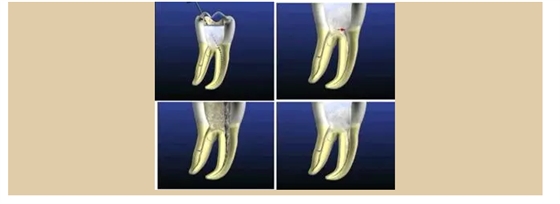

二、根管預(yù)備后形態(tài)

牙體缺損的修復(fù)需要將剩余牙體組織制備成一定形態(tài),以利修復(fù)體的良好固位。根管充填為了致密封閉根管系統(tǒng)也需要良好的根管預(yù)備后形態(tài)。

常規(guī)概念的根管預(yù)備后形態(tài)有: ( 1 )便宜形態(tài)( convenience form )。 ( 2 )保持形態(tài)( retention form )。

常規(guī)概念的根管預(yù)備后形態(tài)有:

( 1 )便宜形態(tài)( convenience form )。 ( 2 )保持形態(tài)( retention form )

( 3 )抵抗形態(tài)( resistance form )。

1. 便宜形態(tài)

便宜形態(tài)是自切端或咬頜面朝向根尖的直線開擴(kuò)尖錐形態(tài),減少污染物推出根尖孔,方便沖洗、根管充填和側(cè)壁施壓。

2. 保持形態(tài)

保持形態(tài)是根尖狹窄部內(nèi) 1 — 2mm 的一段距離,由擴(kuò)大器回轉(zhuǎn)切割而不貼根管壁提拉切割制成,是擴(kuò)大器的原始形態(tài)(近似平行)。在測試主牙膠尖時(shí)給測試者有一個(gè)牽引抵抗 (tugback) 的感覺。

3. 抵抗形態(tài)

抵抗形態(tài)是根管預(yù)備的根尖形態(tài),它是由擴(kuò)大器或根管銼尖端 75 度角自然切割而成。其目的是防止根管充填材超出根尖孔,并且使根尖封閉更加嚴(yán)密。